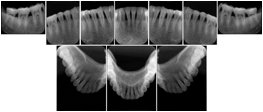

2. A patient requests cosmetic surgery to enhance their facial appearance. The case requires consultation between an orthodontist in New York and an oral surgeon in California. The cephalometric series of 2D projections constructed from a volumetric CT data set that is used for the discussion is arranged by a Structured Display for transfer between the two practitioners.

Cephalometric Series Structured Display

Figure OO-2. Cephalometric Series Structured Display